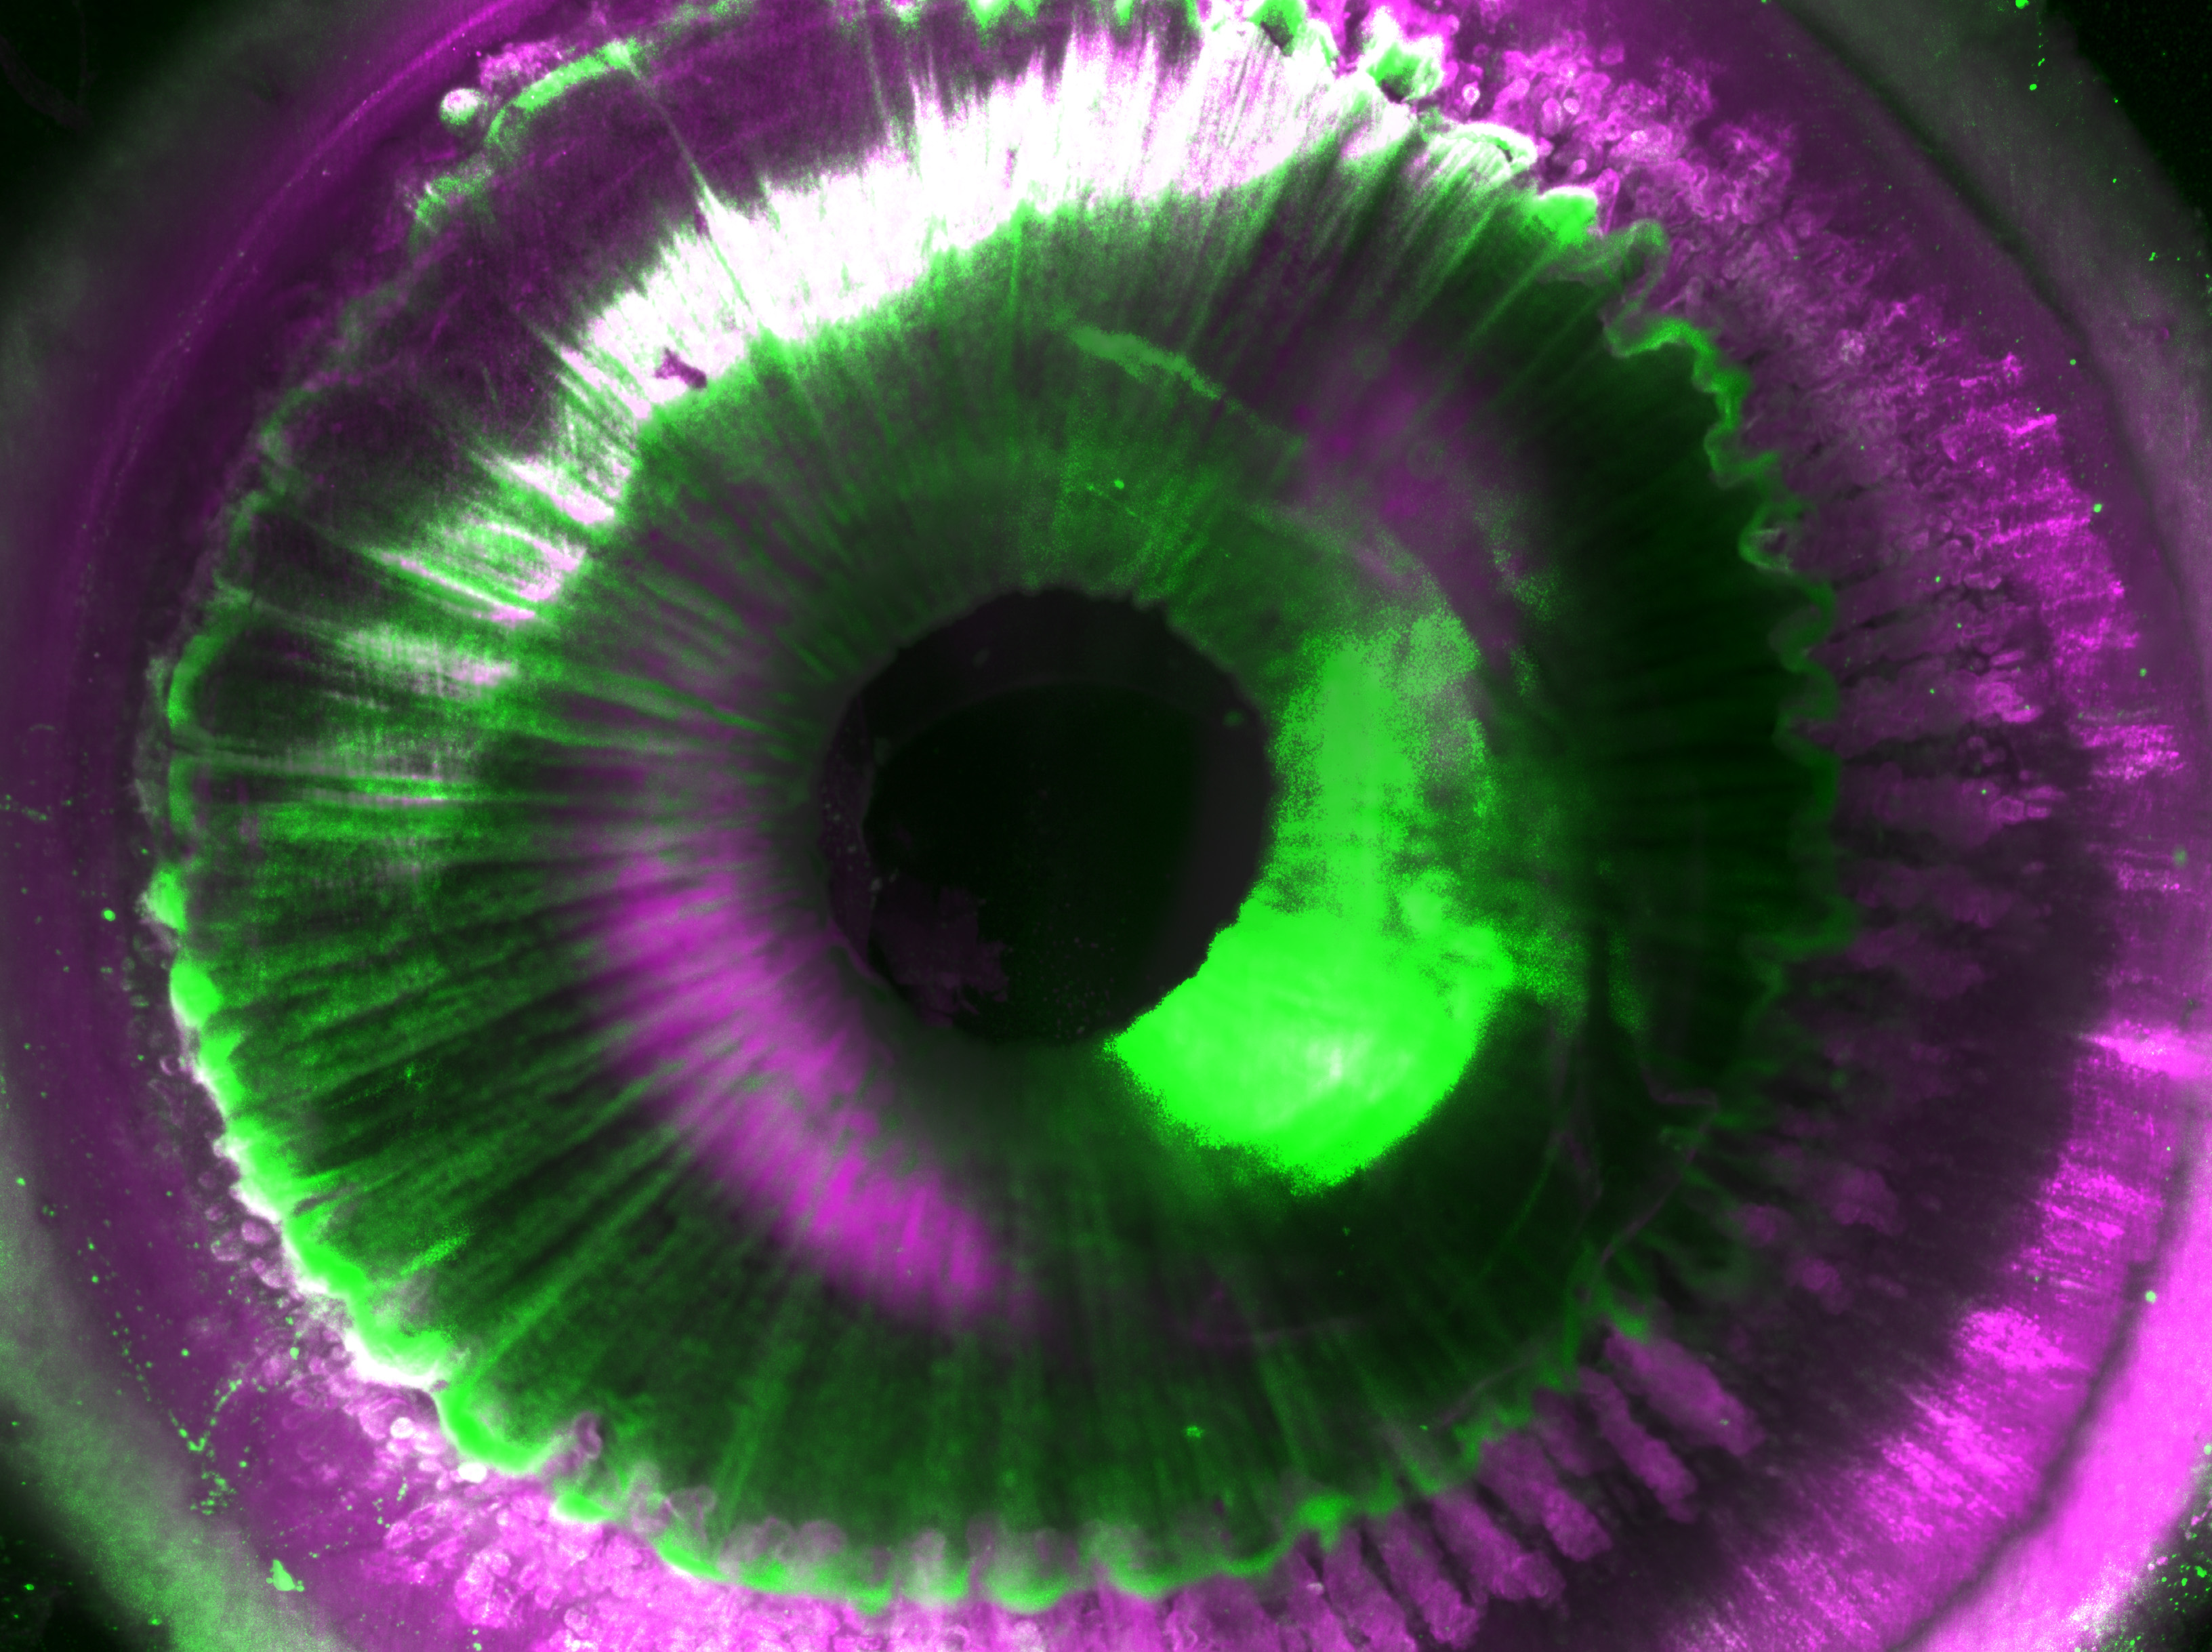

Nachdem die menschlichen Organe, die post mortem vom Labor von Prof. Ingo Bechmann der Universität Leipzig bereitgestellt wurden, transparent gemacht worden waren, mussten die Wissenschaftlerinnen und Wissenschaftler zusätzliche Herausforderungen bewältigen: Die Bildgebung der Organe und die Auswertung der dabei entstehenden Datenmassen. Zunächst entwickelten sie daher gemeinsam mit Miltenyi Biotec ein neues Laser-Scanning-Mikroskop mit einer besonders großen Aufnahmekapazität namens „Ultramicroscope Blaze“. Mit diesem Mikroskop sind Aufnahmen von gesamten menschlichen Organen bis hin zur Größe einer Niere möglich. Anschließend entwickelte das Team zusammen mit Prof. Bjoern Menze von der TUM Deep-Learning-Algorithmen, um Abermillionen von Zellen in 3D analysieren zu können.

Diese Technologie fassten die Forschenden unter dem Namen SHANEL (Small-micelle-mediated Human orgAN Efficient clearing and Labeling) zusammen. „SHANEL könnte sich in naher Zukunft zu einer Schlüsseltechnologie für die Kartierung intakter menschlicher Organe entwickeln. Damit könnten wir sehr schnell viel besser verstehen, wie sich Organe wie unser Gehirn entwickeln und wie sie im gesunden und erkrankten Zustand funktionieren“, erklärt Dr. Ali Ertürk, Direktor des Instituts für Tissue Engineering und Regenerative Medizin am Helmholtz Zentrum München sowie Principal Investigator am Institut für Schlaganfall- und Demenzforschung am Klinikum der LMU.